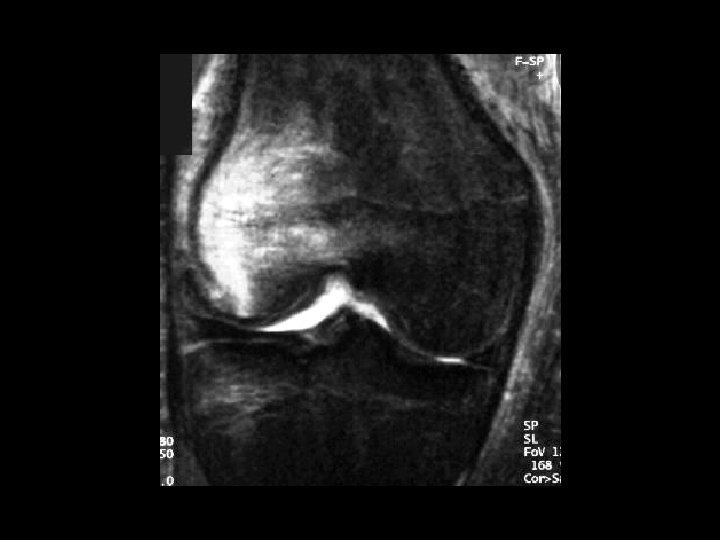

Bucket-Handle Tear • • Findings: – “double PCL sign” - torn meniscus BELOW normal PCL on sag view – Above ACL on cor view – Truncation of medial meniscus – Joint effusion Medial = 3 x lateral Locked knee ddx: – torn ACL, PCL – torn meniscus